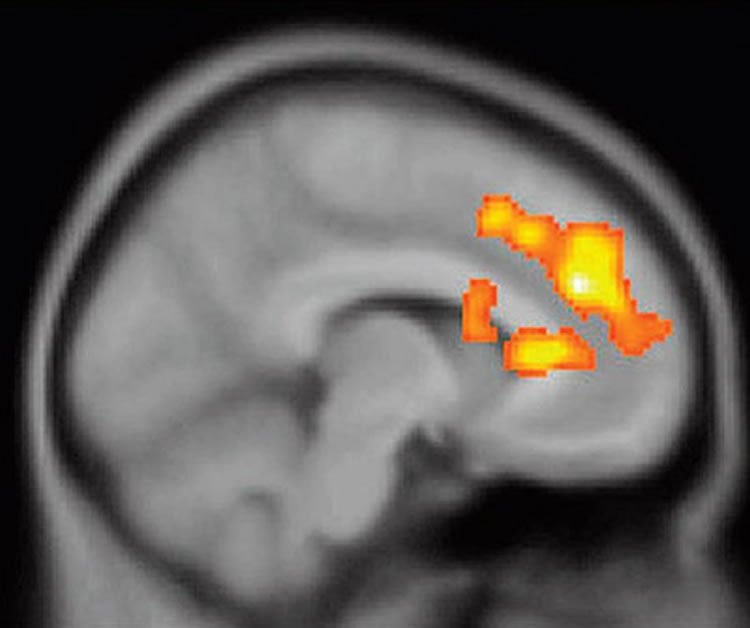

The image shows an mri scan with the dorsal frontal cortex lit up in a bipolar patient.

People with Bipolar Disorder are Bigger Risk Takers

Researchers find circuits involved in pursuing rewarding experiences are more strongly activated in bipolar patients.